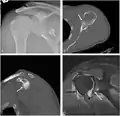

CT scan showing a bony Bankart lesion at the antero-inferior glenoid

Radiograph showing a bony Bankart lesion with stationary fragment at the inferior glenoid

3-D CT reconstruction of a bankart lesion which occurred post anterior shoulder dislocation. This subject's humerus remains mildly superiorly subluxated. Fracture marked by a black arrow.